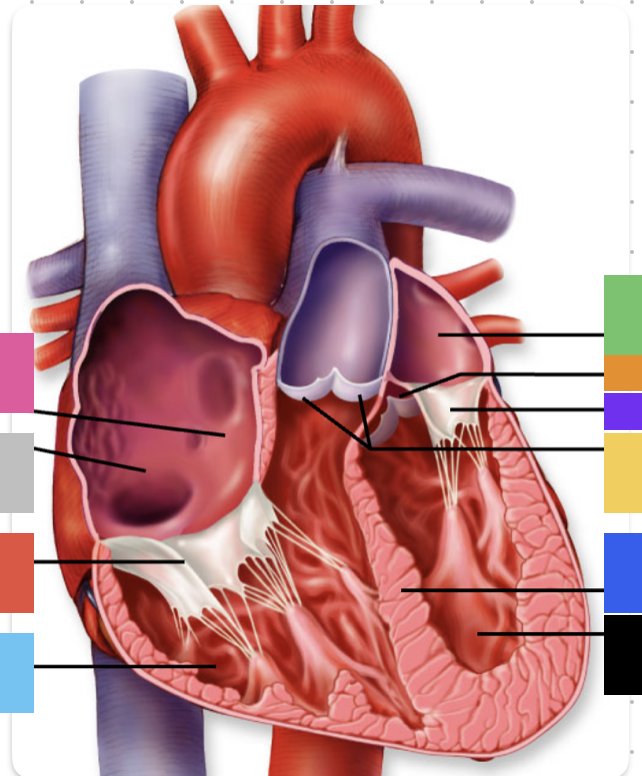

light purple

base

purple

apex

grey

right atrium

pink

right auricle

green

left atrium

green

left auricle

blue

right ventricle

orange

left ventricle

green

coronary (atrioventricular) sulcus

pink

interatrial septum

dark blue

interventricular septum

green

anterior interventricular sulcus

green

posterior interventricular sulcus

orange

aortic valve

yellow

pulmonary valve

red

tricuspid valve (right AV)

purple

bicuspid valve (left AV)

yellow

chordae tendineae

orange

papillary m.

blue

trabeculae carneae - only in ventricles

red

pectinate m. - only in R atrium

pink

fossa ovalis

grey

opening of coronary sinus

green

ligamentum arteriosum

green

fibrous pericardium

blue

parietal pericardium

pink

visceral pericardium (connective tissue) / epicardium (muscle)

purple

myocardium

grey

endocardium

pink

superior vena cava

black arrow

inferior vena cava

black

pulmonary trunk

purple

left pulmonary artery

black

left pulmonary veins

blue

(branches of) right pulmonary artery

yellow

right pulmonary veins

orange

ascending aorta

purple

aortic arch